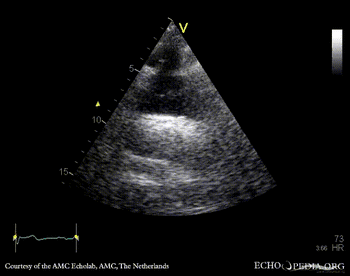

Aortic dissection type A

Suprasternal view: dissection flap in aortic arch Subcostal view: dissection flap in abdominal aorta